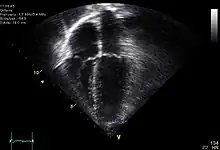

Le cœur est un organe intra thoracique, entouré d'air (les poumons) et d'os (les côtes). Ces deux dernières structures ne laissent pas transmettre les ultrasons, rendant l'examen plus complexe. On se sert ainsi d'un nombre limité de « fenêtres » anatomiques, lieux où le cœur peut être visualisé par l'échocardiographie, sans interposition aérienne ou osseuse.

Le patient est installé torse nu, allongé sur le côté gauche (décubitus latéral gauche). Il n'a pas besoin d'être à jeun. Éventuellement, trois électrodes sont collées afin de disposer d'un tracé ECG simultané. L'examinateur, suivant son habitude, est à la droite ou la gauche du patient. Il applique la sonde d'échographie recouverte d'un gel (permettant un meilleur passage des ultrasons à travers la peau) sur la peau de ce dernier suivant différentes positions constituant les fenètres d'échographie dont les principales sont :

- « Voie apicale », partie inférieure gauche du sternum, là où est perçu le mieux à la palpation le battement cardiaque (« choc de pointe ») ;